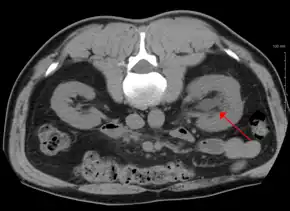

CT scan of bilateral hydronephrosis due to a bladder cancer

- Stone causing hydronephrosis[13]